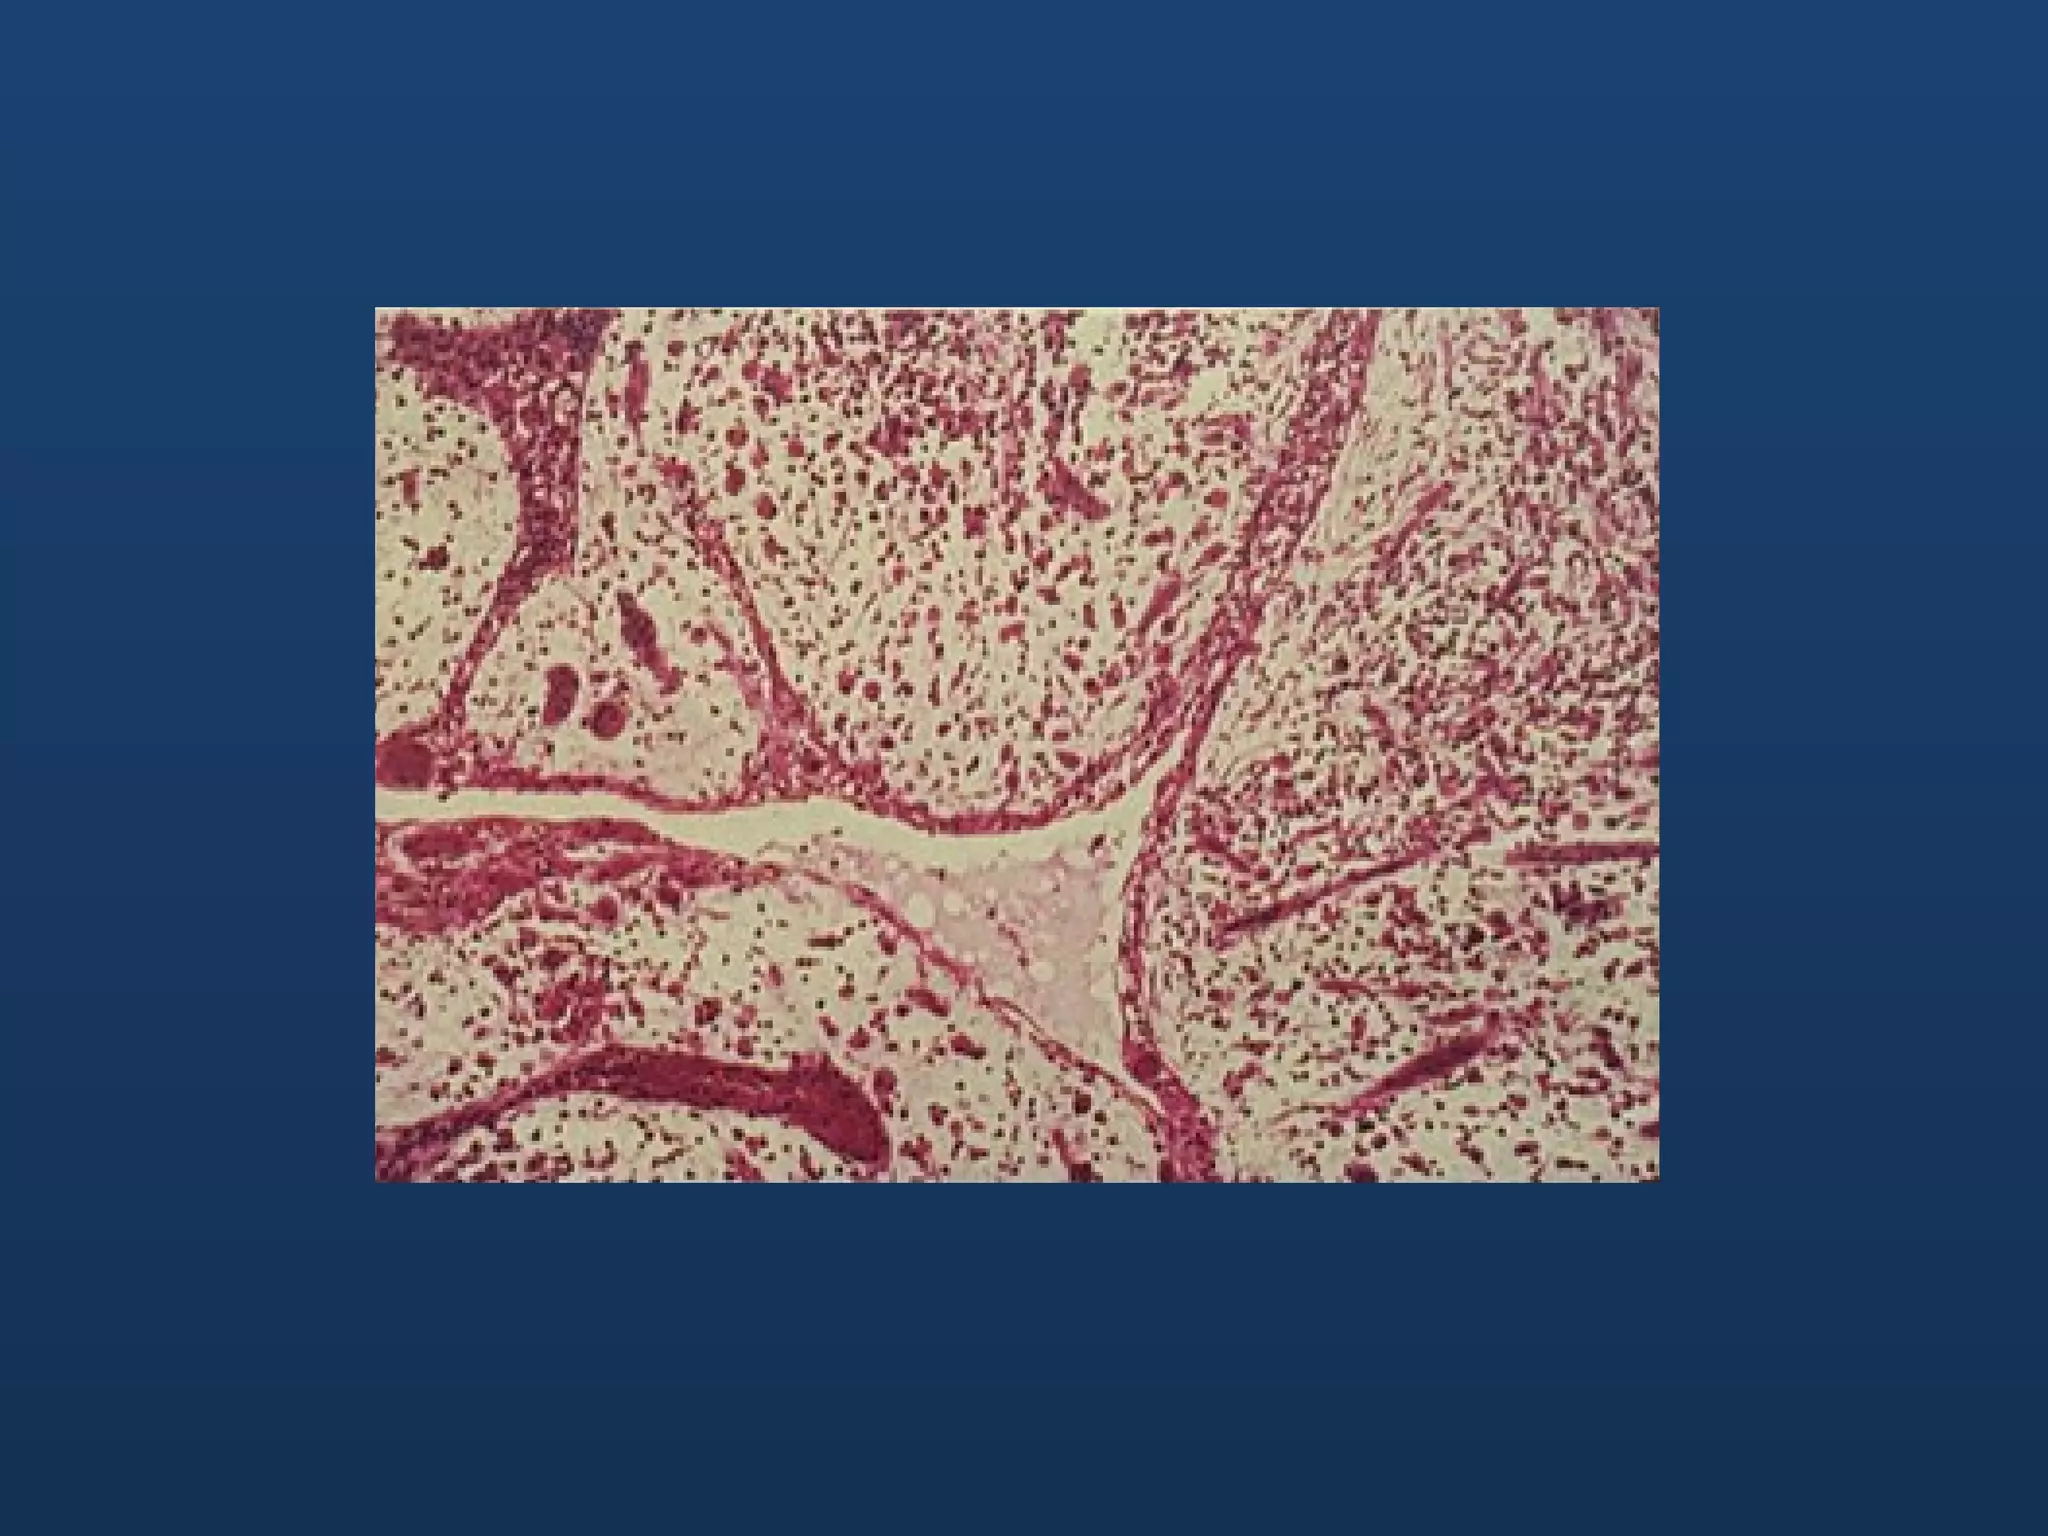

Histopathology • 2 patterns: •Follicular: epithelium arranged into discrete follicles resembling tooth germ • Plexiform type: epithelium is arranged in tangled network and irregular masses

• #58 Follicular ameloblastoma showing islands of neoplastic epithelium, forming separate follicles

• #59 Plaxiform ameloblastoma showing complex pattern of interconnecting epithelial strands